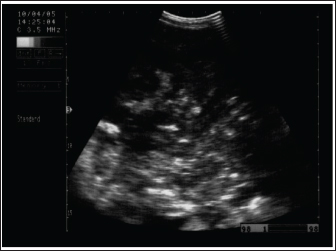

Fig. 5. Ultrasonogram of the cecum, left ventral colon (LVC), and right ventral colon (RVC) in 4 horses with flatulent colic. In A, the cecal wall appears echogenic in the absence of sacculations. In B, the LVC shows an echogenic wall with no sacculations. In C, the RVC shows a thin wall that appears echogenic in the absence of sacculations. In D, RVC appears in the absence of sacculations and with increased wall thickness. These organs contain a large amount of gas, which hinders their visualization.

The cecum of horses with flatulent colic appears thin-walled due to gas distension; absence of sacculations; hypomotility on real-time ultrasonography, and the gases in the cecum prevent visualization of the ingesta inside the cecum (Le Jeune and Whitcomb, 2014). In comparison to healthy horses, the cecum is identified by its sacculations and contractions. The left ventral colon appears with a thin echogenic wall, the absence of sacculations, and the gases inside hinder the visualization of the ingesta. The right ventral colon compared to clinically normal horses shows the absence of sacculations and might be with thin or increased wall thickness, and this agrees well with Scharner et al., (2002), while in control horses it is characterized by the presence of sacculations, bright hyperechoic line, and the inability to identify the entire circumference of its wall (Fig. 5). Horses suffering from severe gas accumulation may collapse where postmortem examination confirms the diagnosis (Tharwat et al., 2008).

In flatulent colic, temperature and respiration are elevated, the pulse rarely exceeds 70 beats /minute, and the mucous membrane is pale. Rectal examination revealed gas-filled portions of the intestines, and distended portions of the jejunum or ileum could be felt as thin-walled loops without sacculations and taeniae. Auscultation of the abdomen revealed decreased peristalsis but not totally absent. In addition, stomach distension may occur resulting in severe signs of pain, sweating, pawing, and hyperactivity (Worku et al., 2017). Horses with flatulent colic usually appear bloated, especially in the right flank, and show signs of severe pain, which may be intermittent or constant with particularly painful spasms. Auscultate pinging sounds are present over the right dorsal flank and midabdominal area (Beccati et al., 2011). The main diagnostic techniques for the tympanic colic in equines are radiography and sonography. Ultrasonographically, Tharwat et al., (2008) reported that flatulent colic bowel appeared distended with gas that prevented visualization of the ingesta inside, and the sacculations disappeared. The peristaltic activity of the gas-distended segment is decreased or absent (Tharwat et al., 2008).